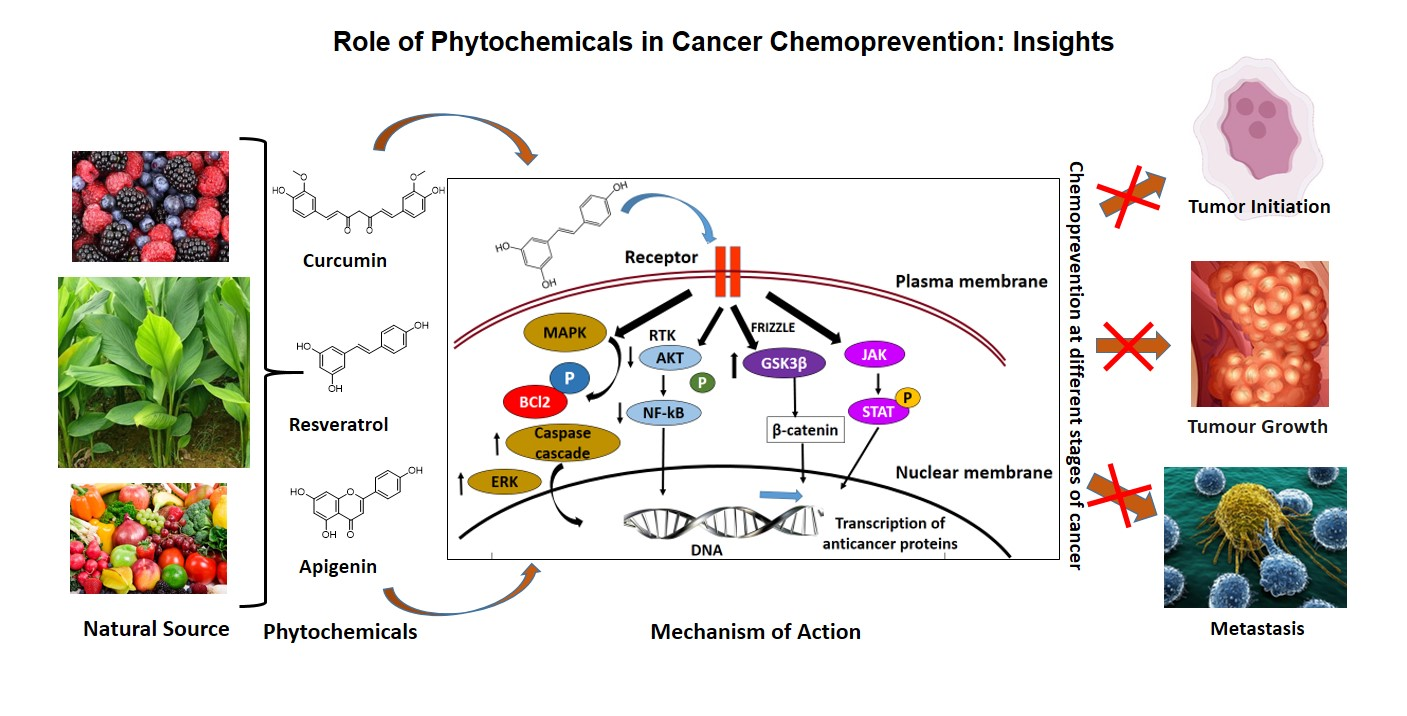

Antioxidants, Free Full-Text